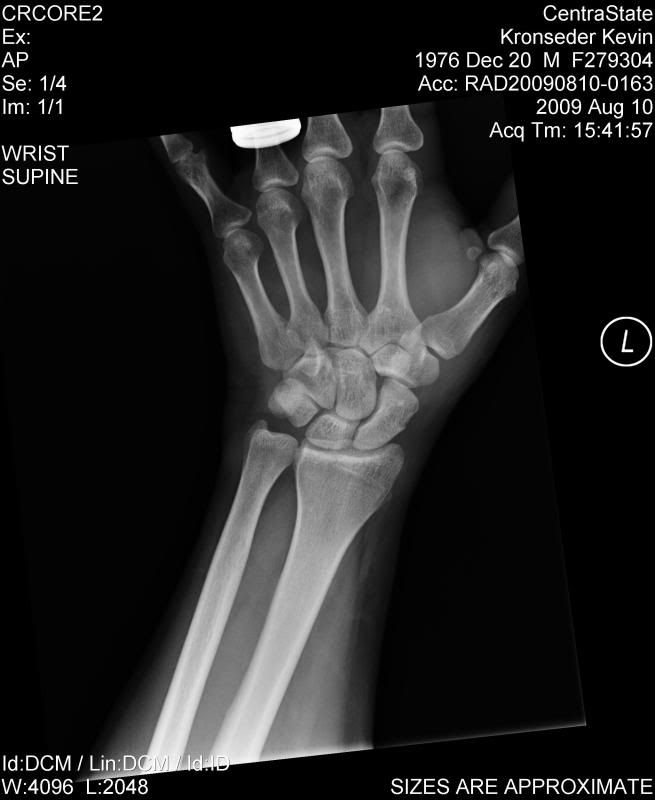

Sprained wrist or scaphoid Health & Fitness ThumperTalk Thumb Socket Surgery Learn about the different surgery options. Total joint replacement has certain advantages over other surgical treatment methods for osteoarthritis of the thumb cmc joint,. It involves removing a bone in the wrist, called the trapezium, and. Thumb carpometacarpal implant arthroplasty aims to preserve thumb length and motion and to provide pain relief and functional recovery after a short postoperative time.. Thumb Socket Surgery.